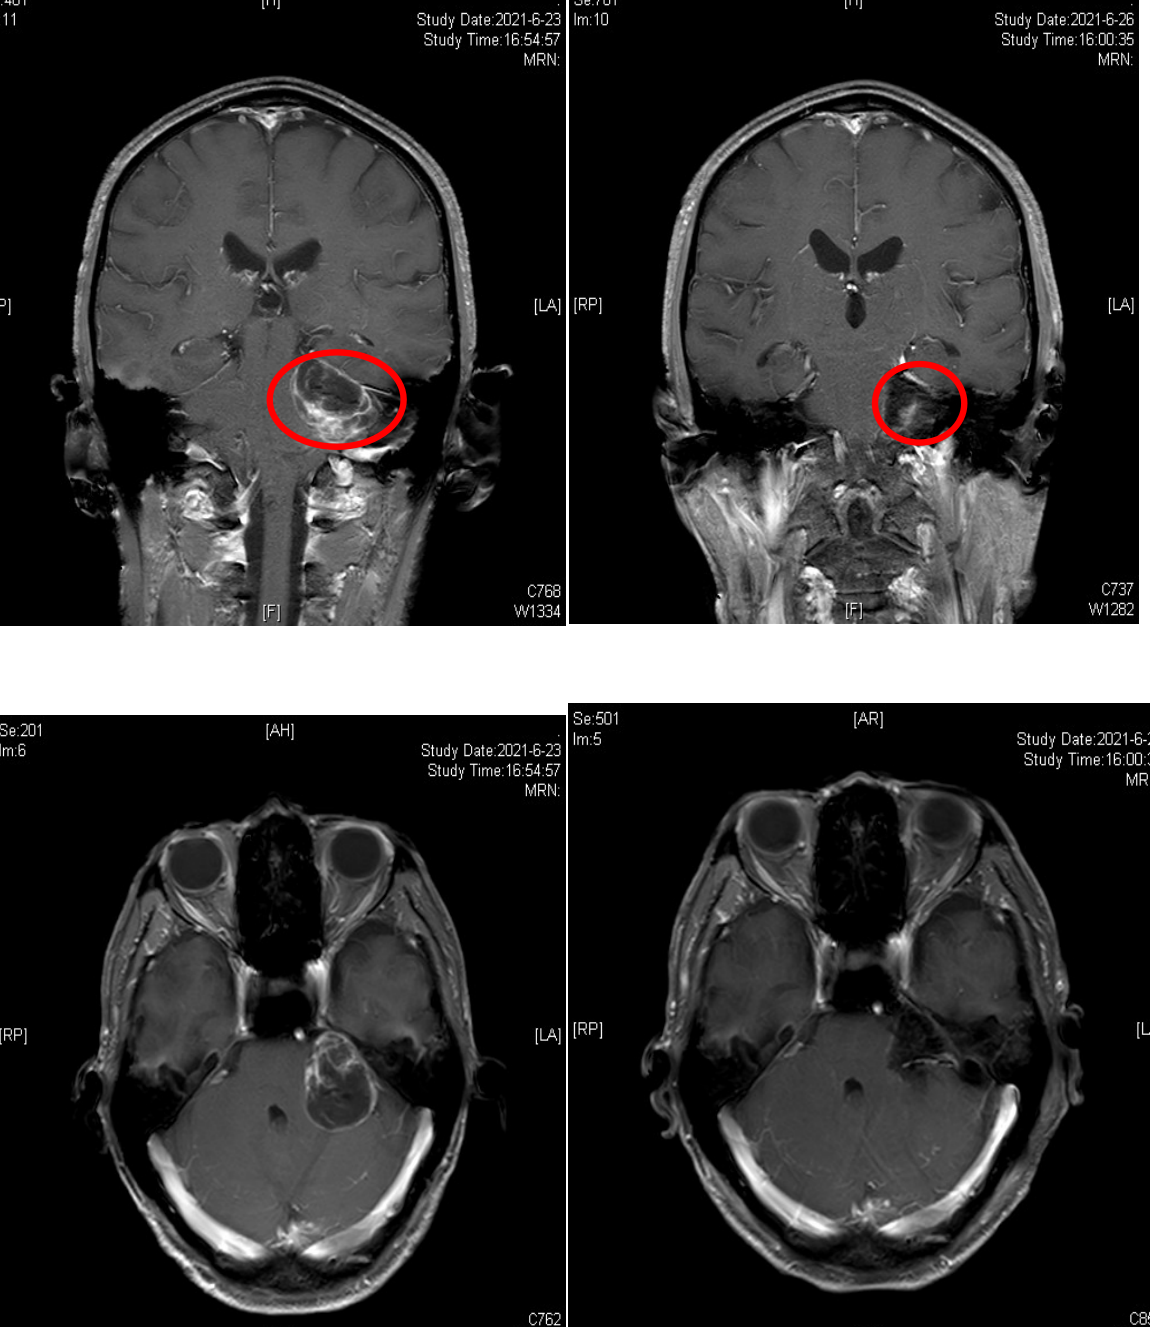

通过头部核磁共振检查显示左侧桥小脑脚区囊实性占位性病灶,大小约4*4cm,是听神经鞘瘤。神经外科副主任、主任医师樊天禹告知患者,听神经瘤属于良性肿瘤,但是会缓慢增长。随着肿瘤的长大,其症状会越来越重,从耳鸣、听力下降直至发展为听力的丧失,甚至压迫周围的神经。因此听神经瘤治疗宜早不宜迟,建议尽早行肿瘤切除手术。

9月10日,长沙市中心医院(南华大学附属长沙中心医院)神经外科手术团队为患者行全麻下颅内肿瘤切除术,术中行面神经电生理监测,手术顺利,术后患者头痛消失,听力及面部麻木好转。

术前与术后对比